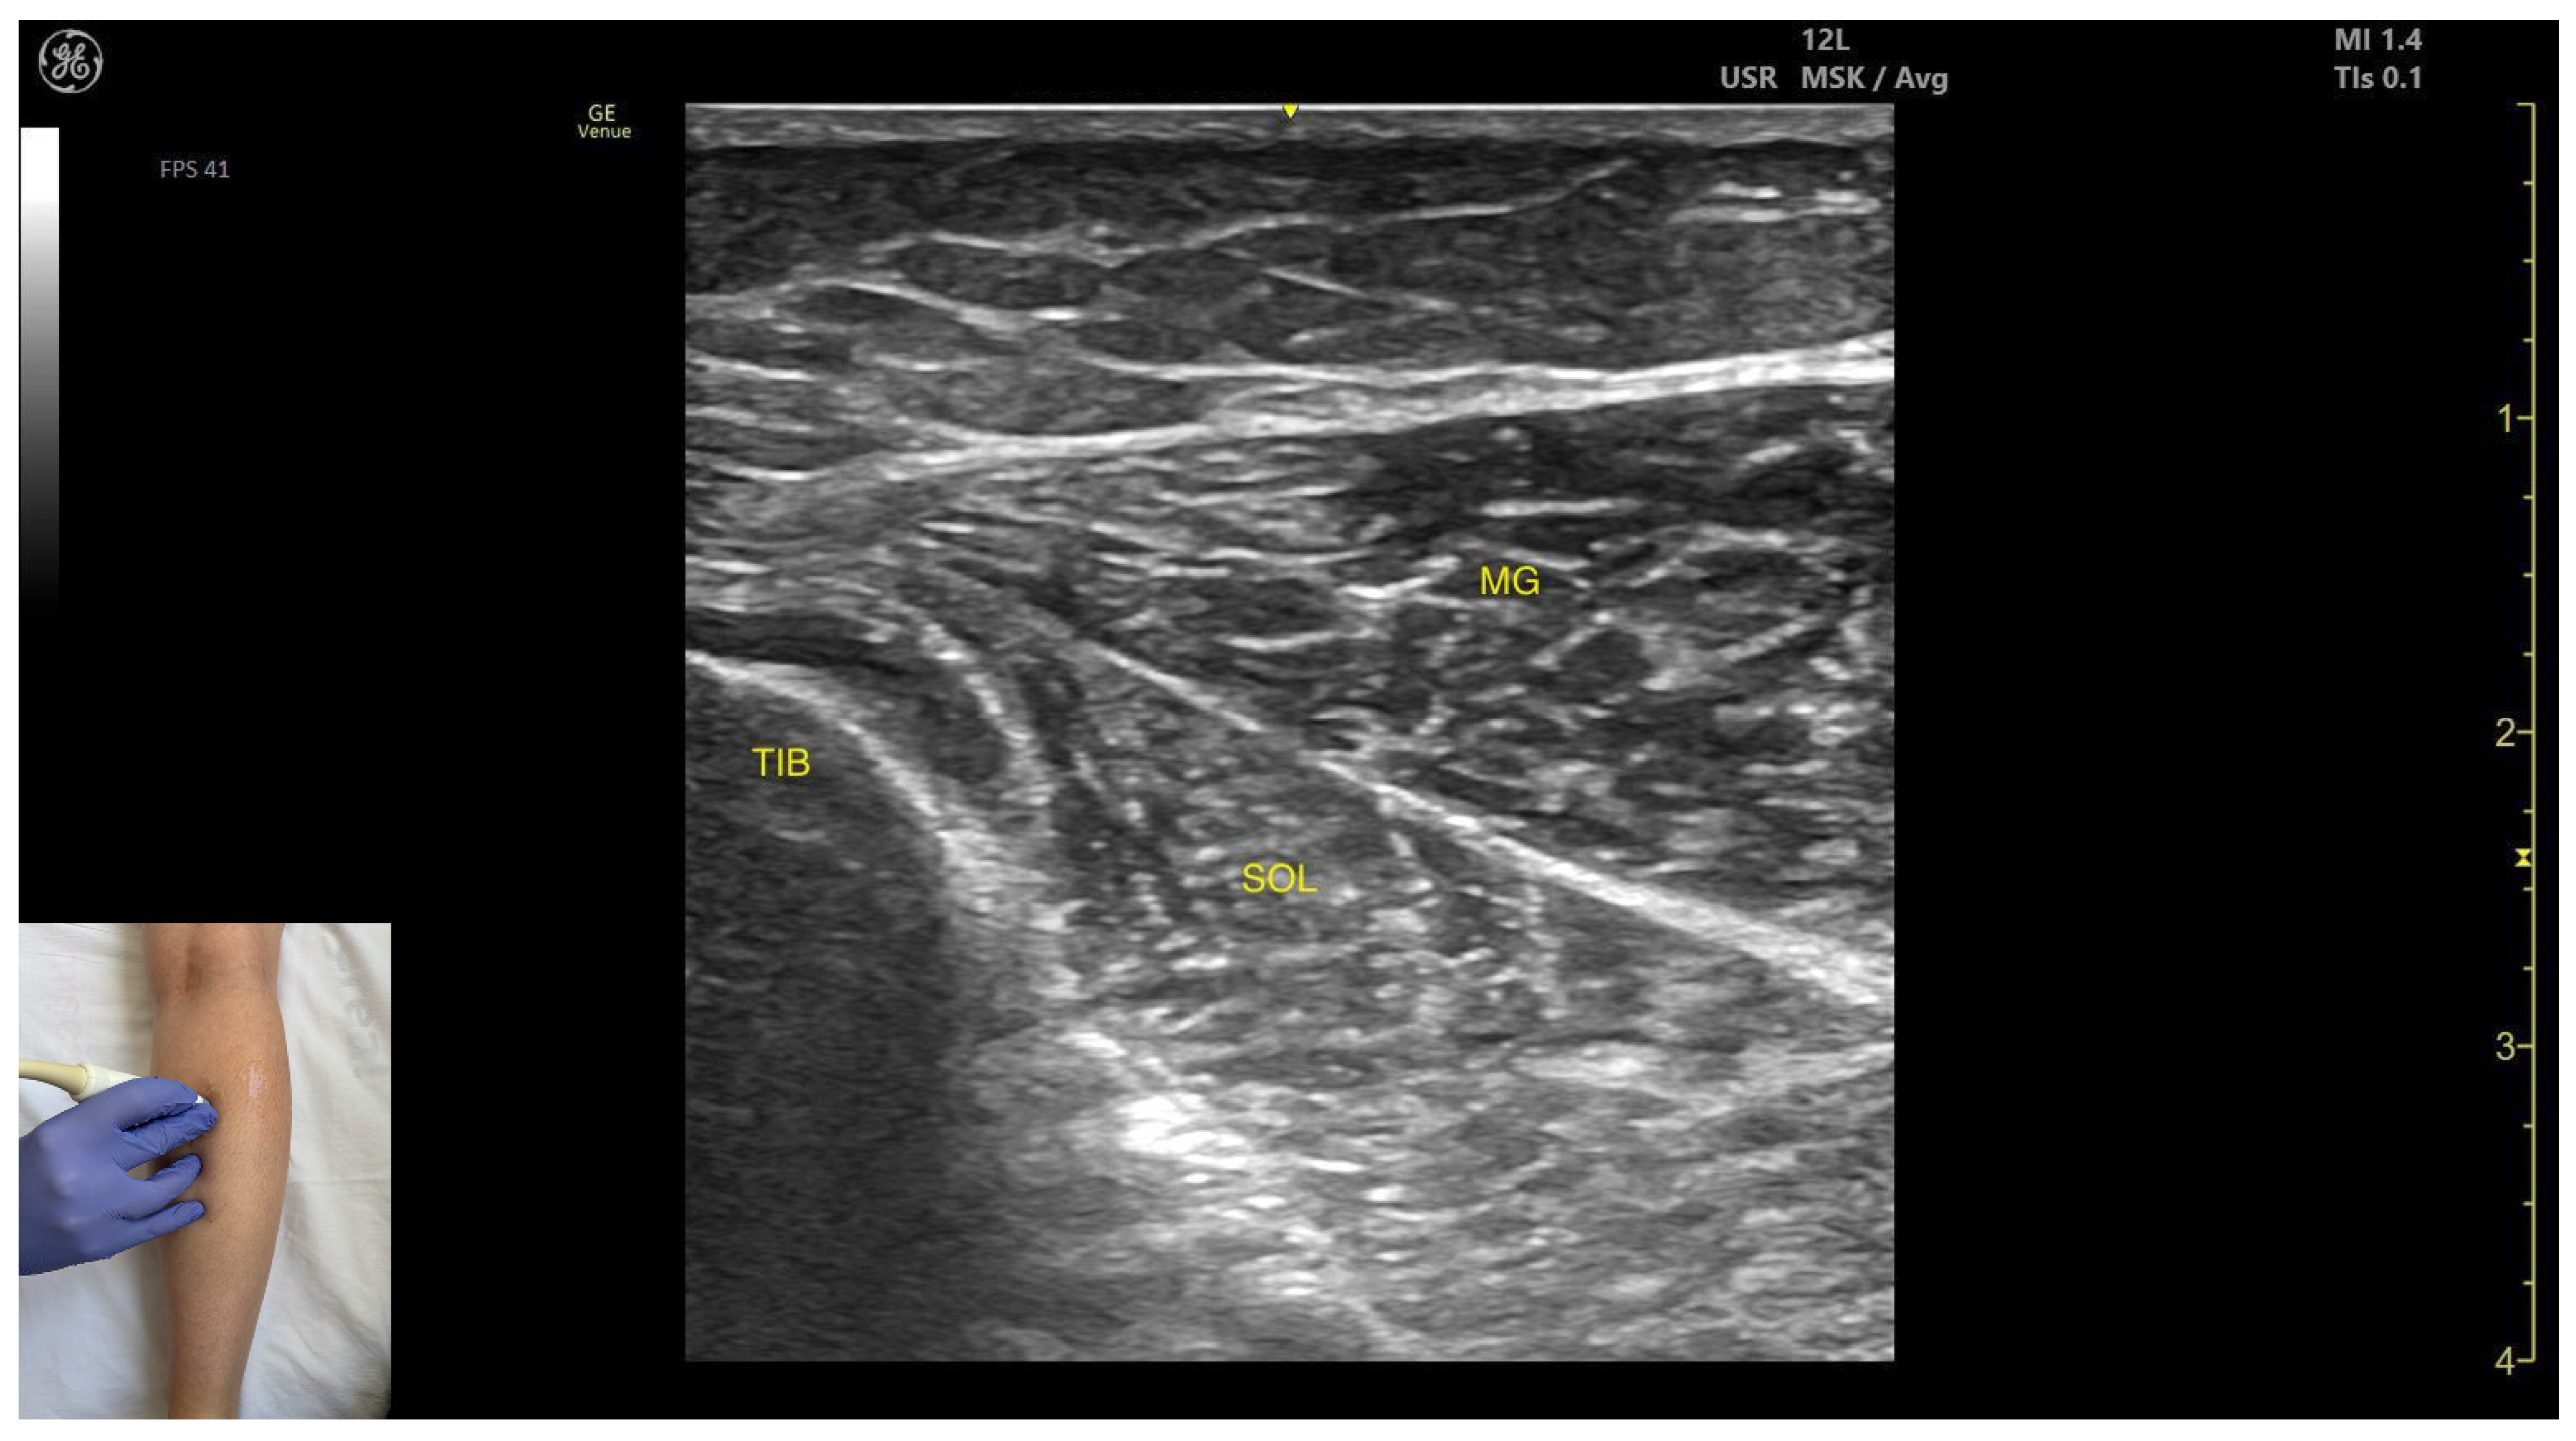

3.2.2. Ultrasound Identification

3.2.3. Key Ultrasound Landmarks:

- Muscle morphology: It appears as a flat muscle in the posterior compartment of the leg.

- Muscle position: At this level, the soleus lies deep to the intersection of the gastrocnemius heads, within which the medial sural cutaneous nerve courses.

- External fascia: A pronounced fascia separates it from the subcutaneous plane, gastrocnemius muscles, and the plantaris muscle/tendon (if present), which is relevant during BoNT-A injection.

- Dynamic evaluation: During dynamic evaluation, scanning laterally reveals enlargement of the lateral gastrocnemius head, and deep to the soleus, the neurovascular bundle emerges, comprising the posterior tibial artery, the two posterior tibial veins, and the posterior tibial nerve. Medial scanning highlights enlargement of the medial head of the gastrocnemius (MG), while the neurovascular bundle maintains its anatomical course. The soleus, a monoarticular muscle acting exclusively at the ankle joint, is optimally assessed with the knee flexed; this positioning diminishes gastrocnemius involvement, allowing for isolated evaluation of soleus contractile activity via EMG or dynamic ultrasound imaging. Muscle contraction is visible during plantar flexion maneuvers of the foot at the ankle joint.

| Medial Head of Gastrocnemius | ~8 cm distal to the popliteal crease, on the medial side | Medial sural cutaneous nerve (superficial), soleus and plantaris muscle/tendon if present (deep) | Transverse scan on the posterior aspect of the leg | Avoid medial sural cutaneous nerve injury |

| Soleus | ~8 cm distal to the popliteal crease on the midline | Gastrocnemius (superficial) and plantaris muscle/tendon (if present); posterior tibial artery, tibial veins, and the posterior tibial nerve (deep) | Transverse scan on the posterior aspect of the leg | Avoid neurovascular injury |